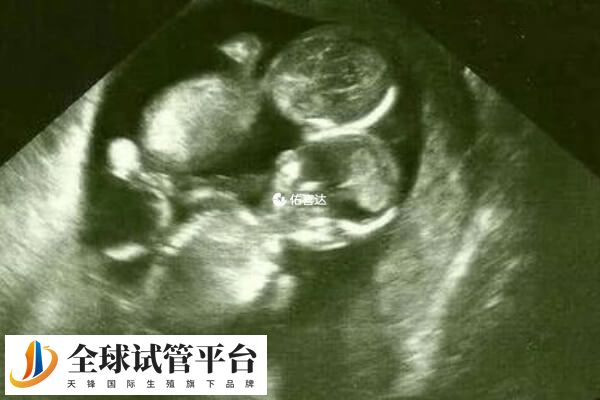

三胞胎减一胎是有可能成功的,这是因为随着减胎技术的不断发展,目前减胎成功率可达90%以上(妊娠周数越小,成功率越高)。而且在临床上有较多成功案例,如义乌首例三胞胎减胎术,成功将三胎减为双胎,术后胎儿发育正常。不过是否减胎还要根据个人情况及医生建议决定,不可盲目选择。

一般来说,三胎减胎手术的成功率通常在90%左右,同时患者若是通过超声引导操作,还可有效降低并发症风险。不过因个体之间存在较大的差异,所以针对部分复杂病例(如胎儿共用一个胎盘或存在血管吻合),则需采用射频消融技术,以此减胎的成功率才可达预期。